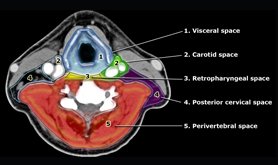

CT neck scan checks the soft tissues of the neck inclusive of the muscles, tonsils, throat, thyroid, airways, adenoids and other glands. The blood vessels and upper spinal cord can also be observed. When a CT neck scan is taken, the spine, airways, carotid muscles as well as salivary and thyroid glands are also viewed by doctors. In some cases, the jaw bone, mouth and tongue, pharynx and larynx, including the vocal cords are shown.

Neck CT tests are often used to study a lump or mass or to look for big lymph nodes or glands in the neck. CT of the neck is the preferred exam when evaluating the soft tissue structures present in the neck. The CT neck scan gets over by 15 minutes